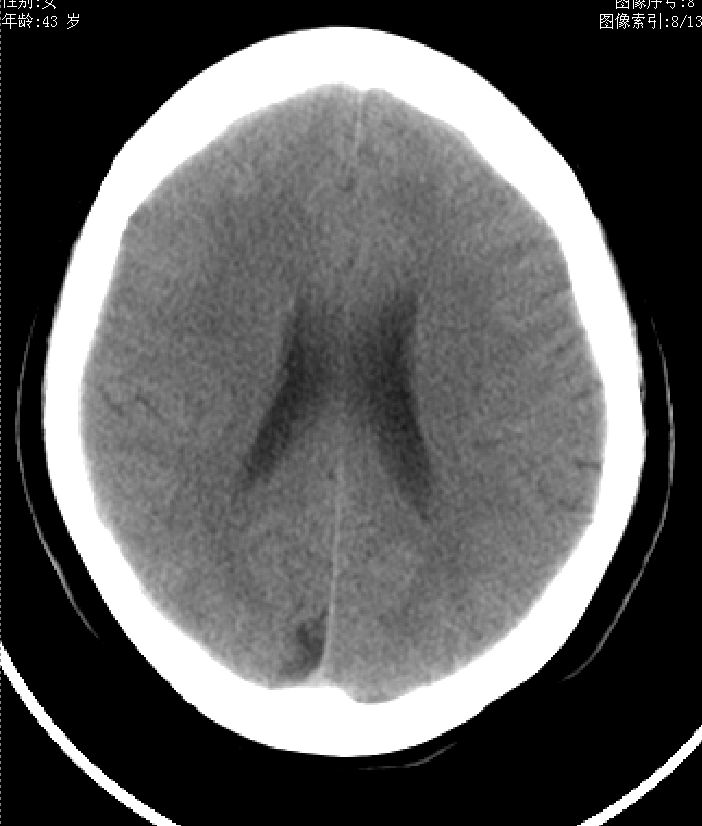

43岁,女性,头晕、语言含糊1天伴左侧肢体麻木,有高血压病史,bp160/100hg,余(-)。

右顶上小叶脑沟

考虑右侧顶叶脑软化灶。

考虑右侧半卵圆中心陈旧性梗塞.